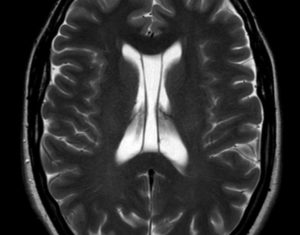

На снимках визуализируются паренхиматозные кисты с гладкими закругленными границами и минимальным отражающим сигналом. Глиозные кисты составляет менее 1% от внутричерепных кистозных образований.

На рентгене или КТ определяется полость, заполненная ликвором, с отеком окружающих тканей. Данные полости не отвердевают. Их необходимо отличать от арахноидальной кисты, расширения периваскулярного пространства, нейроцистицеркоза (заражение личинками бычьего цепня), эпендимальных и эпидермоидных кист.

При КТ обследовании они определяются в виде полостей с ликвором, окруженные тканями с признаками отечности. Обычно такие кисты себя практически не проявляют, обнаружить их можно случайно при диагностике других заболеваний.